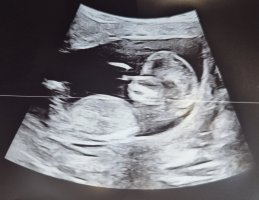

Såå søtBle målt til 8+2 så 1 dag fremMen til venstre kan dere se en muskelknute i livmora… noen som har erfaringer med det? Da jeg leste om det ble jeg litt bekymret og det ga plutselig mening hvorfor jeg har hatt vondt rundt menstrasjon og mistet noen ganger…

Men til venstre kan dere se en muskelknute i livmora… noen som har erfaringer med det? Da jeg leste om det ble jeg litt bekymret og det ga plutselig mening hvorfor jeg har hatt vondt rundt menstrasjon og mistet noen ganger…